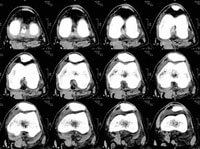

Mako Robotic-Arm Assisted Technology provides you with a personalized surgical plan based on your unique anatomy. First, a CT scan of the diseased knee joint is taken. This CT scan is uploaded into the Mako System software, where a 3D model of your knee is created. This 3D model is used to pre-plan and assist your surgeon in performing your joint replacement procedure.